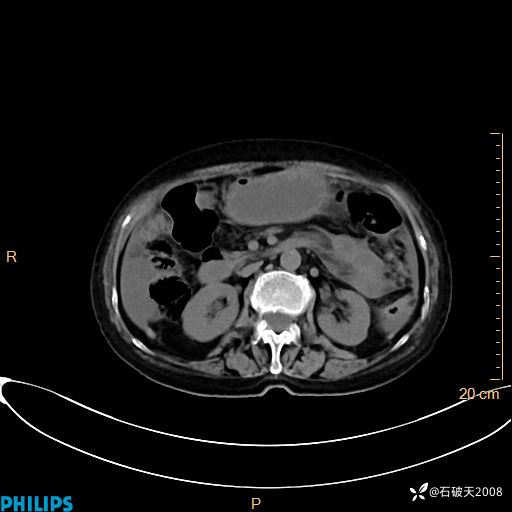

平扫